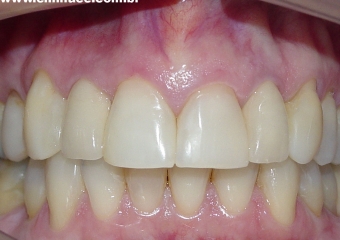

Imagem inicial e final de caso de agenesia dental, reabilitado com implante unitário no elemento 12

Prótese fixa sobre implante, finalizado em janeiro de 2010